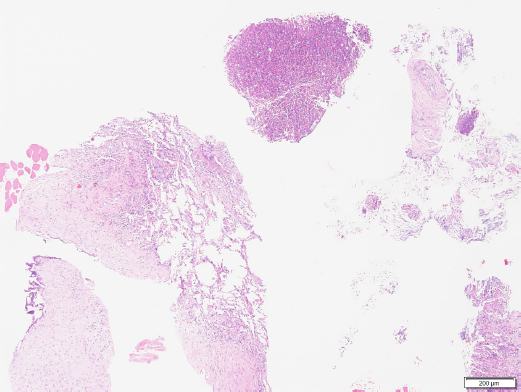

Histopathologic results of the sample confirmed marked, multifocal, chronic, neutrophilic, and eosinophilic granulomatosis with a fibrous capsule (Figs. 4 and 5).

Histochemical stains including, Gram for bacteria, Ziehl-Neelsen for acid-fast organisms, Periodic Acid–Schiff, and Grocott Methenamine Silver for detection of fungal organisms, were applied to the tissue sampled and all failed to reveal any infectious agents. A negative bacterial culture supported the results observed in histochemistry. The result was consistent with pulmonary pyogranuloma compatible with EPG. Corticosteroid treatment was started with a daily dose of prednisolone (Macrolone, Mavlab) at 2 mg/kg PO q 24 hours for 2 weeks.

Fig. 4. Histopathology of the pulmonary mass via a Trucut biopsy. Overview revealing fibrosis and an eosinophilic multifocal inflammatory component (40× magnification). Image courtesy of Dr. May TSE from CityU VDL, Hong Kong.